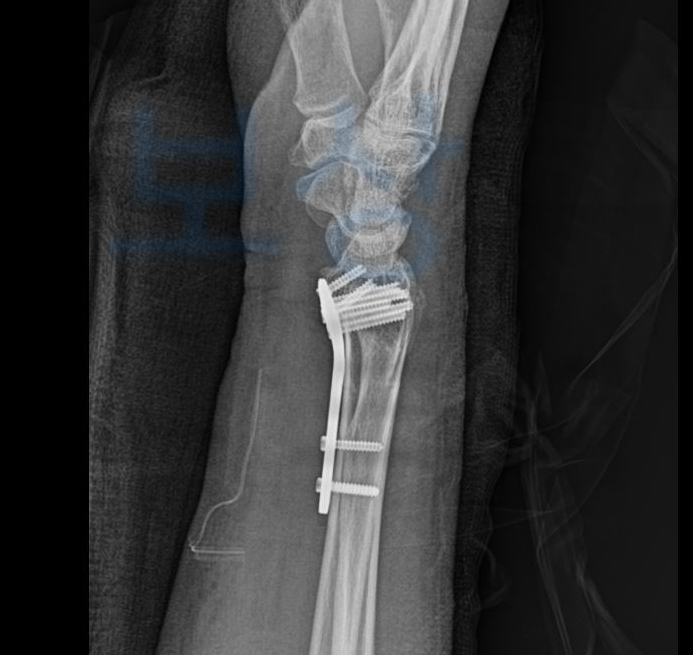

실제 저희가 진행해드렸던 김@@님은 버스요금을 내신 뒤에 의자를 향해 가시다가 버스가 급정거를 하는 바람에 뒤로 넘어지며 손목을 다치는 사고를 당하셨는데요, 이처럼 내 실수인지/ 버스의 잘못인지 과실 산정이 애매한 상황에서!

이 과정 중 노동능력상실률 확인하기 위해

전문의의 맥브라이드방식의

후유장해진단서도 필요하죠. 합의금은 지금의 질환이